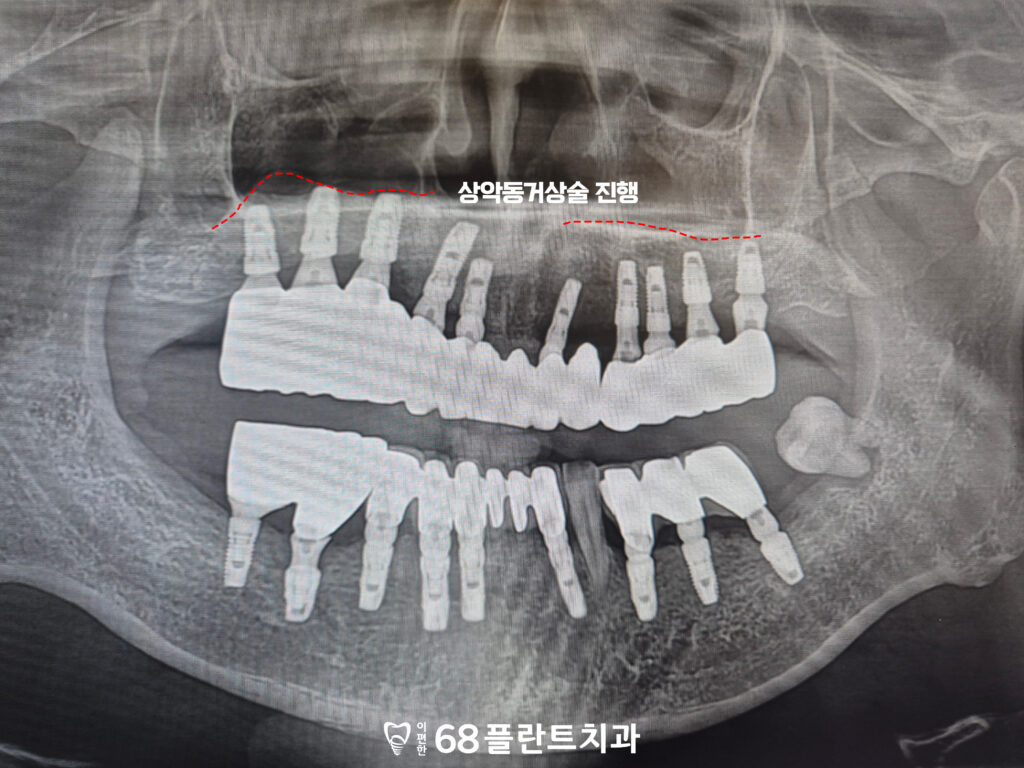

<상악동거상술 및 임플란트 진행>

먼저 발치가 필요한 치아들은 모두 정리한 후,

상악 구치부의 부족한 골을 보완하기 위해

상악동거상술을 시행하였으며,

이후 안정적인 골 형성이 확인된 뒤

임플란트를 식립하는 순서로

치료를 진행하였습니다.

그리고 임플란트와 이식한 뼈가

충분히 유착되어 안정화된 것을 확인한 후,

최종 보철 치료를 진행하여

기능적·심미적 회복을 이루며

치료를 마무리하였습니다.

<타원 임플란트 보철 진행>

또한 타원에서 임플란트가 식립된 부위도

현재 상태를 면밀히 평가한 후,

주변 조직과의 안정성을 확인하였으며,

이상 소견이 없는 것을 확인한 뒤

보철 치료를 이어서 진행하였습니다.

위쪽 임플란트 보철에 맞춰 교합을 조정하여

위, 아래의 균형을 맞추고,

전체적인 저작 시 힘이 고르게

분산될 수 있도록 했는데요.

이를 통해 해당 부위 역시

정상적인 저작 기능을

회복할 수 있도록 하였습니다.

그리고 사랑니까지 전부 발치한 후

전체적인 치료를 마무리할 수 있었습니다.